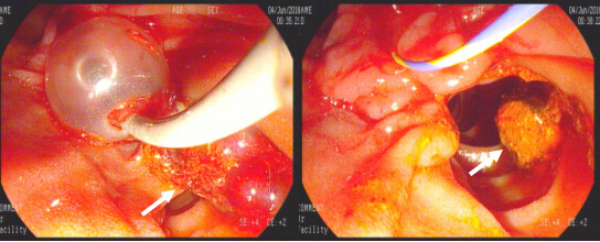

2016年7月13日,由赵刚主治医师操作,在左爱丽护士长、李婵护士、杨龙宝博士的协助下,在密切监护患者生命体征的同时对其实施ERCP手术。术中可见患者十二指肠降部有多发巨大憩室,十二指肠乳头位于其中一憩室内,属于憩室内乳头的情况,操作稍有不慎即可能引起十二指肠穿孔。一次性顺利插管至胆总管并造影,确认了胆管中结石的大小约1.2cmx1.4cm,位于肝总管处(结石可能由于插管及造影发生了位移),同时也发现由于憩室的压迫,患者胆管走形异常扭曲。我们对该患者的十二指肠乳头进行了小切开并以1.2cm胆管扩张球囊进行扩张,后以取石球囊顺利自胆管中取出巨大成型结石一枚,再次造影胆管内未见残存结石,遂置入鼻胆管,整个操作过程用时仅30分钟。患者术后第2天即恢复正常饮食,腹痛症状基本消失,目前已经顺利出院。

造影可见结石位于肝总管处(黄箭头所示) 胆道扩张球囊进行扩张的过程

取石气囊取出巨大成型结石1枚(白箭头所示)